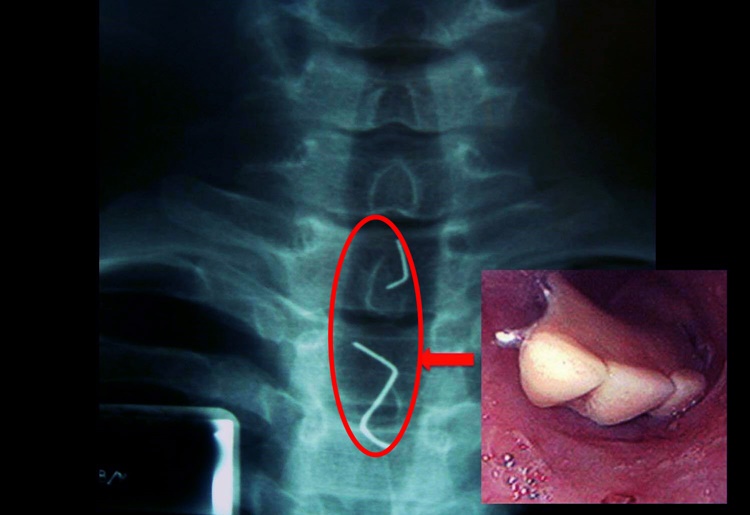

In the photos, it can be seen that the victims showed x-ray results with findings of dentures inside their body. The victims accidentally swallowed the artificial teeth during unexpected circumstances.

Another Filipino named Marvin swallowed the dental implant during a watermelon eating contest.